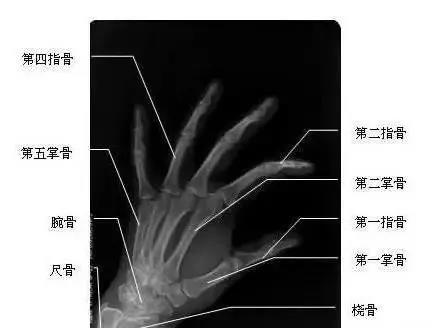

我們先來看一下雙手漂亮的“骨感”圖,這是雙手主要骨頭組成部分。骨頭外面覆蓋了肌肉、血管、神經(jīng)、筋膜、皮膚等組織。腱鞘,就是指纖維鞘+指滑膜鞘的雙層套管樣結(jié)構(gòu),對肌肉的肌腱起約束、支持和滑車等作用。所謂腱鞘炎,就是指肌腱及其周圍覆蓋組織發(fā)生炎癥。腱鞘炎最常發(fā)生于手部或腕部,但也可發(fā)生于身體其他部位,如踝部。